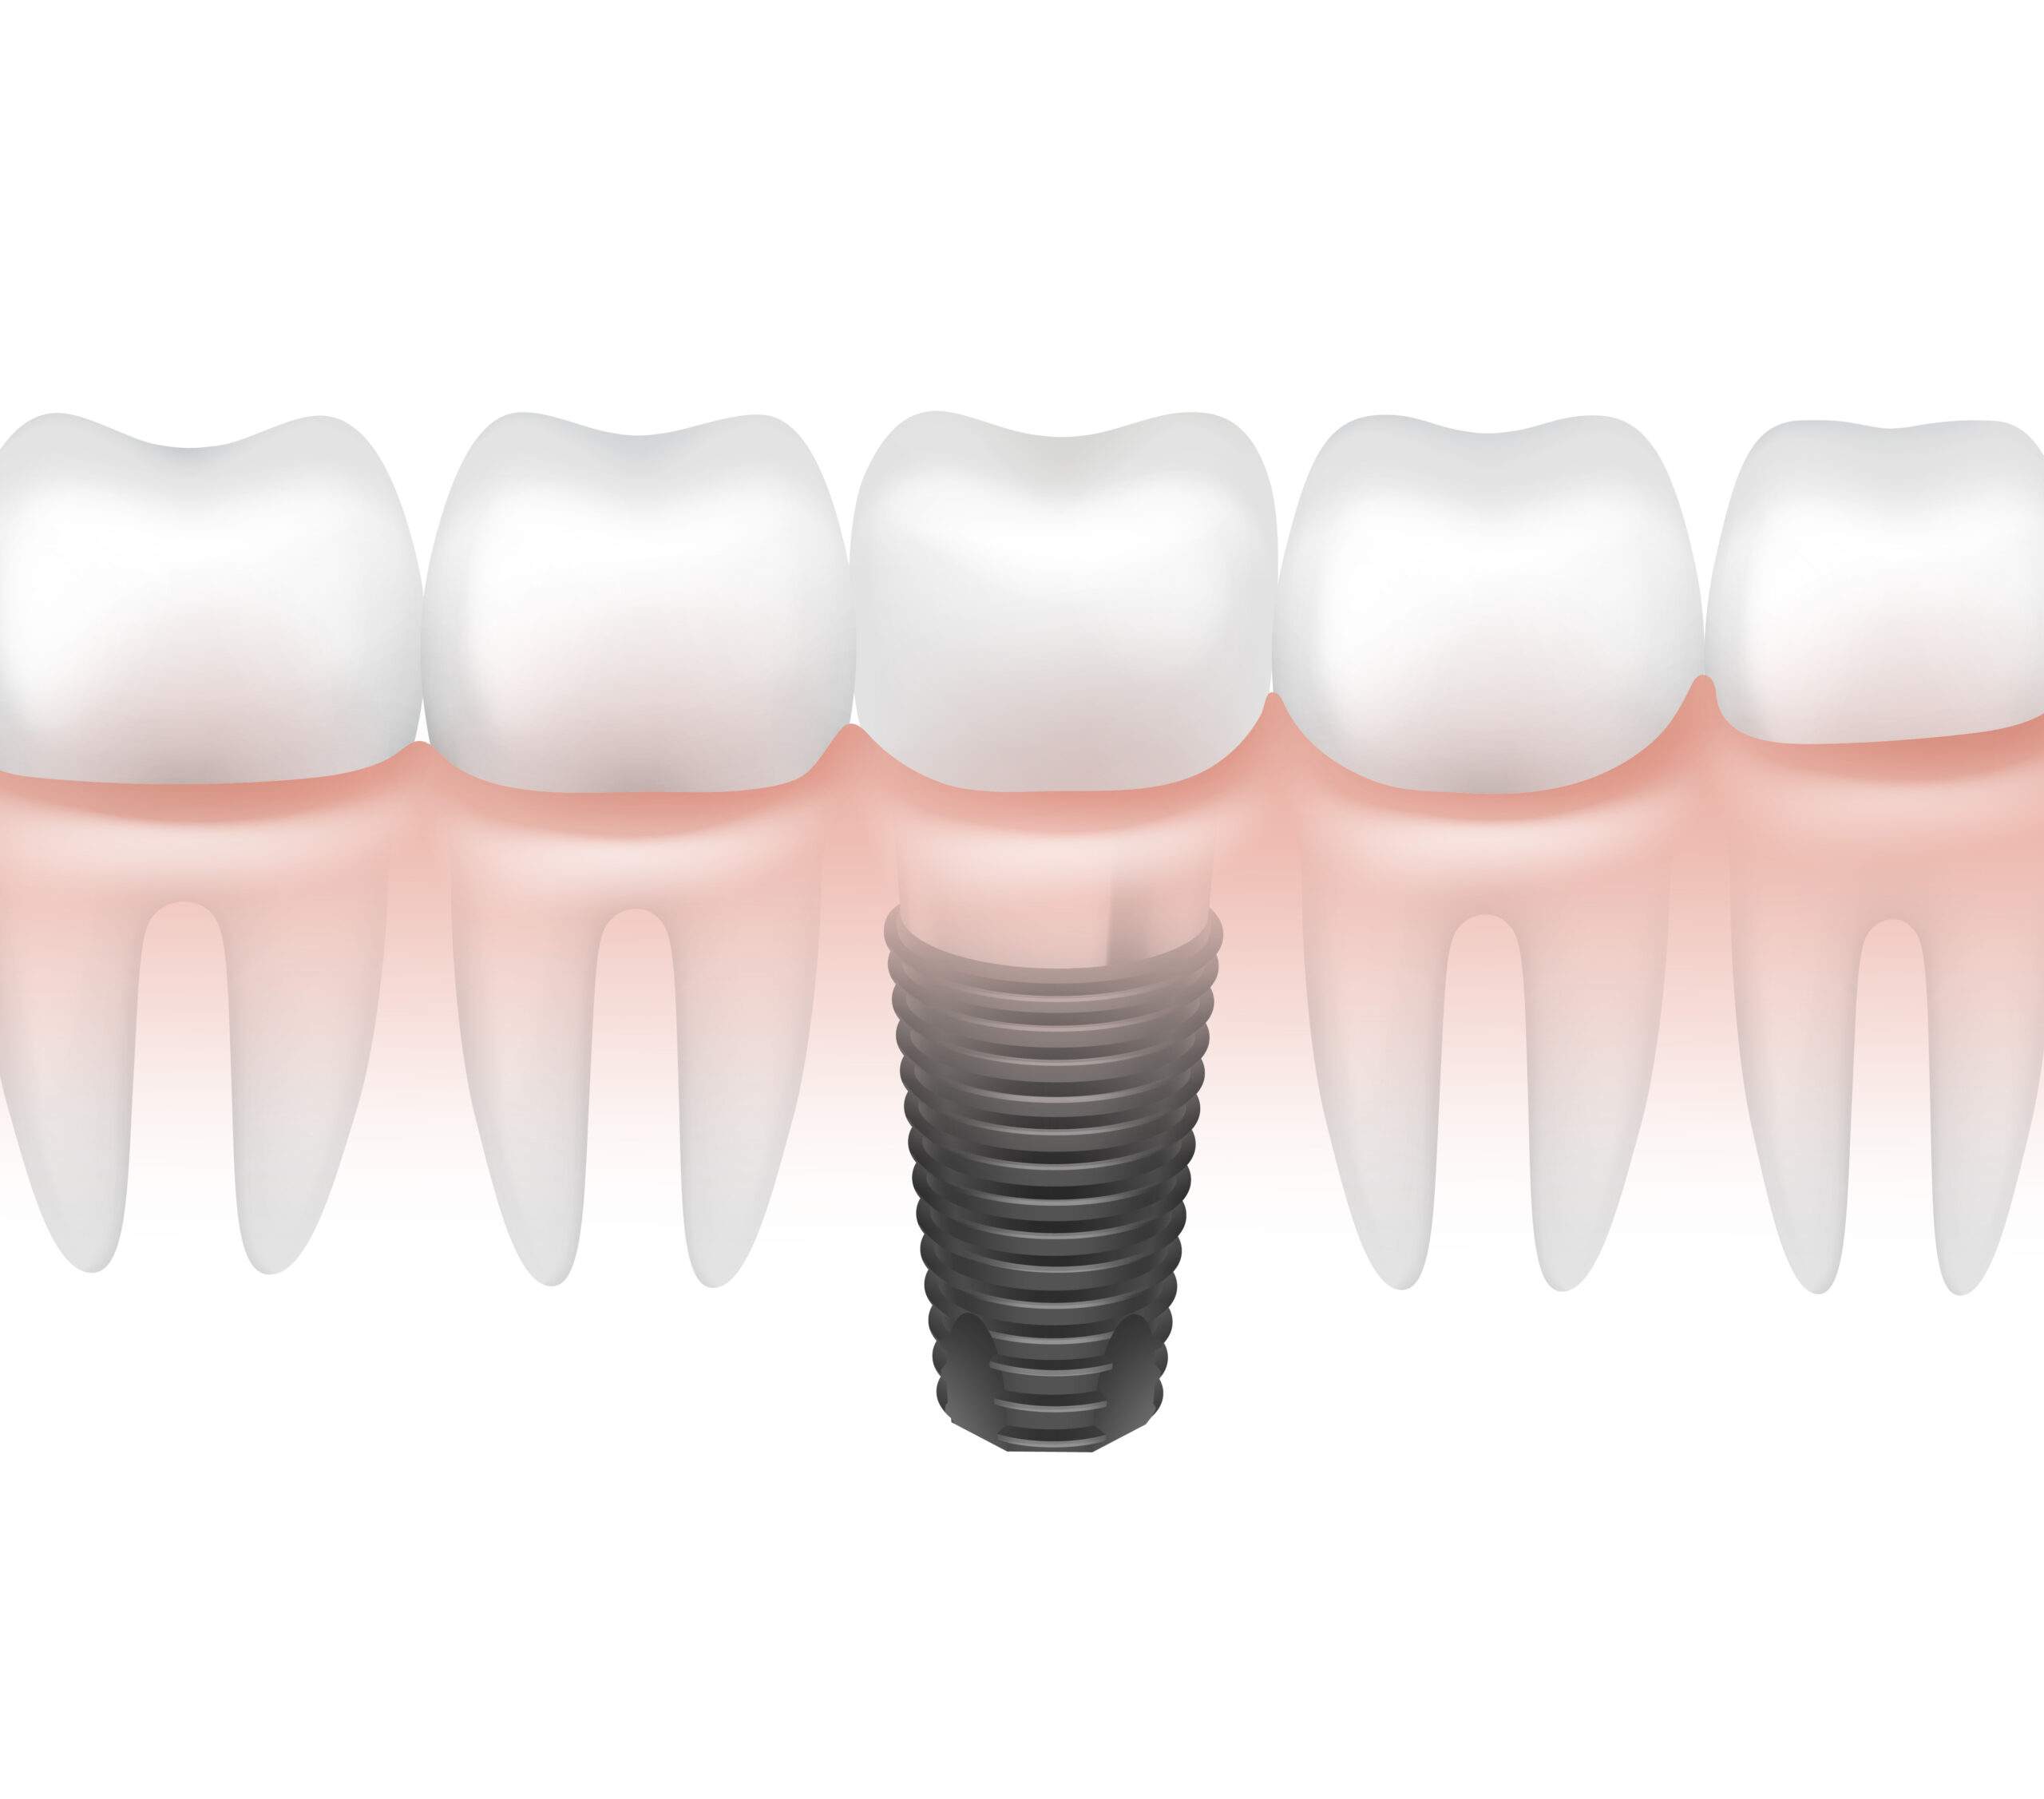

Implantes dentales: una solución estable para recuperar la sonrisa

Implantes dentales: una solución estable para recuperar la sonrisa La pérdida de uno o varios dientes es una situación más común de lo que parece. ...